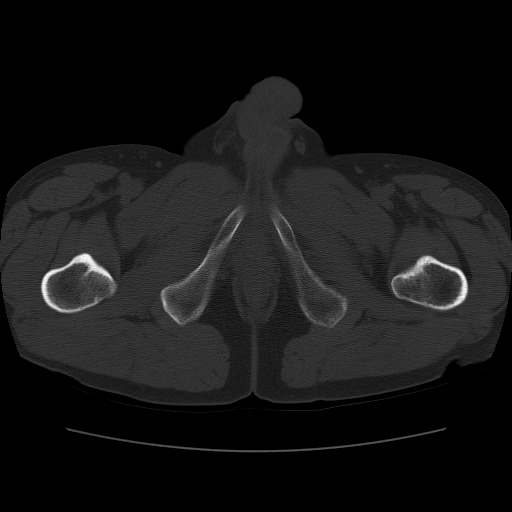

标题: CT11650:左髋病变,请会诊. [打印本页]

标题: CT11650:左髋病变,请会诊.

左髋疼痛不适近半年,局部无红肿热.无明确外伤病史.黄酒每天二餐.

考虑左侧股骨头缺血性坏死.(常期饮酒引起代谢障碍?)

左侧股骨头缺血性坏死;很典型。

左侧股骨头缺血性坏死,支持!图像有些乱。

“局部无红肿热.无明确外伤病史.黄酒每天二餐”。考虑左侧股骨头缺血性坏死。